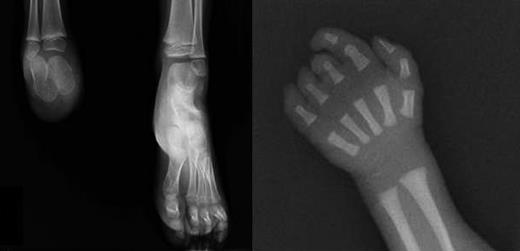

X-rays of limb defects in patients. (Left) Foot x-ray of subject III-1, showing absence of the right foot; the calcaneus and astragalus, that are absent in the father, are present although smaller than the controlateral ones. (Right) X-ray of right hand in subject III-3, showing absence of the last phalange of 2° digit and last 2 phalanges of 3° to 5° digits.